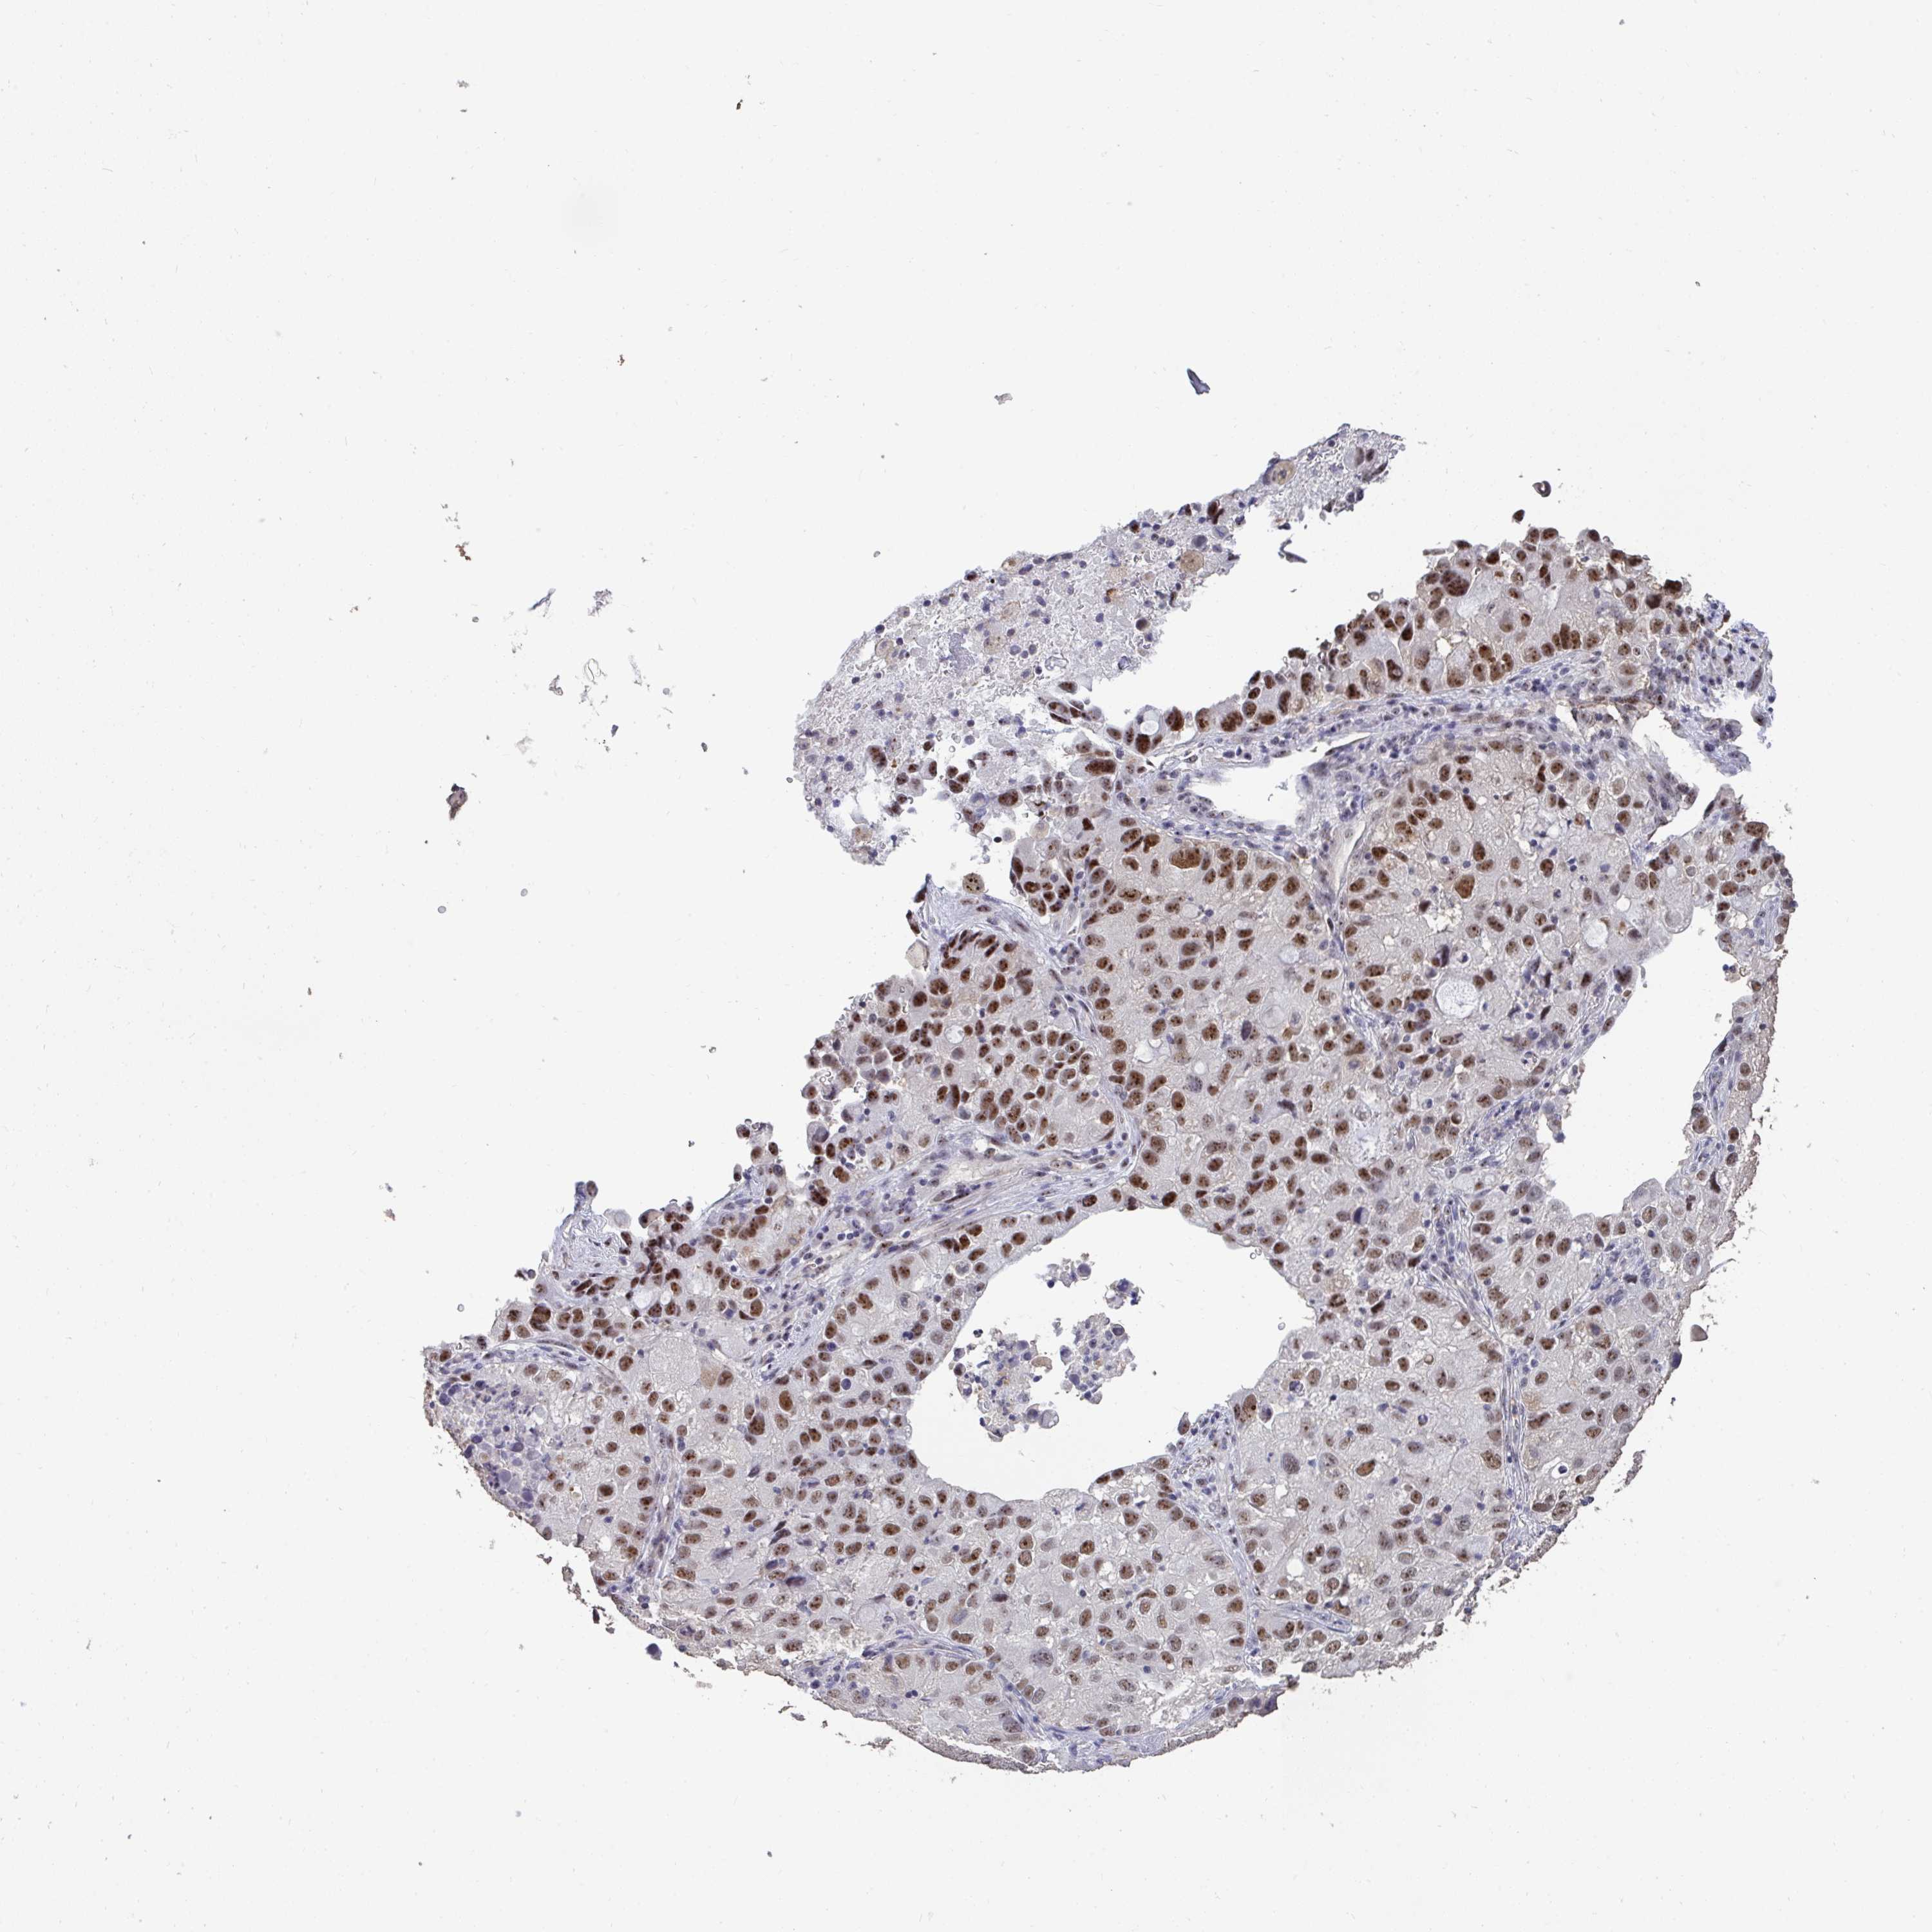

LUNG ADENOCARCINOMA (TCGA) - Interactive survival scatter ploti

The Survival Scatter plot shows the clinical status (i.e. dead or alive) for all individuals in the patient cohort, based on the same data that underlies the corresponding Kaplan-Meier plots. Patients that are alive at last time for follow-up are shown in blue and patients who have died during the study are shown in red.

The x-axis shows the expression levels (FPKM) of the investigated gene in the tumor tissue at the time of diagnosis. The y-axis shows the follow-up time after diagnosis (years). Both axes are complimented with kernel density curves demonstrating the data density over the axes. The top density plot shows the expression levels (FPKM) distribution among dead (red) and alive patients (blue). The right density plot shows the data density of the survived years of dead patients with high and low expression levels respectively, stratified using the cutoff indicated by the vertical dashed line through the Survival Scatter plot. This cutoff is automatically defined based on the FPKM cutoff that minimizes the p-score. The cutoff can be changed by dragging the vertical line or by entering a cutoff value in the square labeled "Current cut-off".

Under the Survival Scatter plot the p-score landscape (black curve; left axis) is shown together with dead median separation (red curve; right axis). Dead median separation is the difference in median mRNA expression between patients who have died with high and low expression, respectively. It is calculated as follows: median FPKM expression of dead patients with high expression - median FPKM expression of dead patients with low expression. This is intended to aid the user in visually exploring custom cutoffs and the associated p-scores and dead median separation.

Individual patient data is displayed and can be filtered by clicking on one or more of the category buttons on the top of the page. Categories describing expression level and patient information include: high, low, alive, dead, female, male and tumor stages. The scale of the x-axis can be toggled between linear and log-scale by clicking on the "x log" button. Mouse-over function shows TCGA ID, patient information and mRNA expression (FPKM) for each patient.

& Survival analysisi

Kaplan-Meier plots summarize results from analysis of correlation between mRNA expression level and patient survival. Patients were divided based on level of expression into one of the two groups "low" (under cut off) or "high" (over cut off). X-axis shows time for survival (years) and y-axis shows the probability of survival, where 1.0 corresponds to 100 percent.

SENP3 is potential prognostic, high expression is unfavorable in Lung Adenocarcinoma (TCGA)

Best expression cut offi

Based on the FPKM value of each gene, patients were classified into two groups and association between prognosis (survival) and gene expression (FPKM) was examined. The best expression cut-off refers the FPKM value that yields maximal difference with regard to survival between the two groups at the lowest log-rank P-value. Best expression cut-off was selected based on survival analysis .

When clicking on this number, the vertical dashed line indicating cut-off, the interactive survival plot, and the Kaplan-Meier curve will be adjusted to show results based on the best expression cut-off.

: 33.19